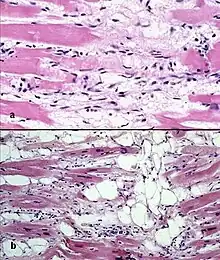

Il existe deux lésions pathologiques dans la dysplasie ventriculaire droite arythmogène : l'infiltration adipeuse et l'infiltration fibro-adipeuse :

- l'infiltration adipeuse est confinée au ventricule droit. Elle implique une substitution partielle ou quasi complète du myocarde par du tissu adipeux, sans amincissement de la paroi. Le ventricule gauche et le septum inter-ventriculaire (paroi séparant les deux ventricules) sont généralement épargnés. Il n'y a pas d'infiltration inflammatoire. Une dégénérescence des myocytes est mise en évidence dans la moitié des cas ;

- l'infiltration fibro-adipeuse implique le remplacement des myocytes par du tissu fibro-adipeux. Il existe une infiltration inflammatoire (principalement de lymphocytes T). L'atrophie du myocarde est liée aux lésions et à l'apoptose. Ceci conduit à un amincissement de la paroi libre du ventricule droit.

Une biopsie transveineuse du ventricule droit peut être spécifique, mais peu sensible. De faux-positifs existent, par exemple lors d'un alcoolisme chronique ou au cours de la dystrophie musculaire de Duchenne. De faux-négatifs sont également possibles, car la maladie progresse typiquement de l'épicarde vers l'endocarde d'une part et d'autre part, de par la nature segmentaire de la maladie (qui n'atteint que certaines zones du myocarde). De plus, de par la finesse de la paroi libre du ventricule droit, beaucoup de prélèvements sont réalisés au niveau du septum inter-ventriculaire, qui lui, n'est habituellement pas atteint par la maladie. Une biopsie compatible avec le diagnostic devrait comporter plus de 3 % de tissu adipeux, plus de 40 % de tissu fibreux et moins de 45 % de myocytes. Le dosage d'une protéine, la plakoglobine, intervenant dans la structure du cytosquelette, dans l'échantillon biopsiée, pourrait être un indice important en faveur de la maladie s'il est abaissé[32].